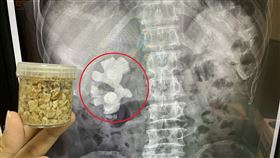

男腰痛血尿 8公分鹿角大結石塞腎臟

新冠肺炎防疫期間適逢夏季結石好發季節,有結石病史的民...

男每天尿30多次 尿路驚卡2顆結石

澎湖一名69歲退休公務人員的李阿伯,前陣子每天排尿次...